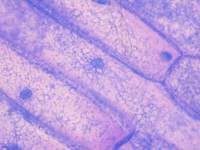

细胞库 / 细胞培养、试剂、实验室仪器 / 设备、技术服务、耗材

原代细胞